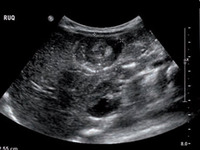

Intussuscepção: sonograma transversal do abdome mostrando sinal de "donut" (anéis concêntricos dentro do lúmen de uma alça distendida do intestino)

Adaptado do Student BMJ. 2008;16:76

Colecistite: ultrassonografia de colecistite aguda e presença de cálculos biliares

Do acervo de Dr. Charles Bellows